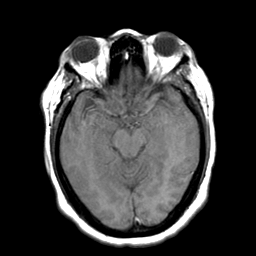

Cerebral hemorrhage, MR Study mr-t1 -- Slice #10

[Home][Help][Clinical] Slice 10